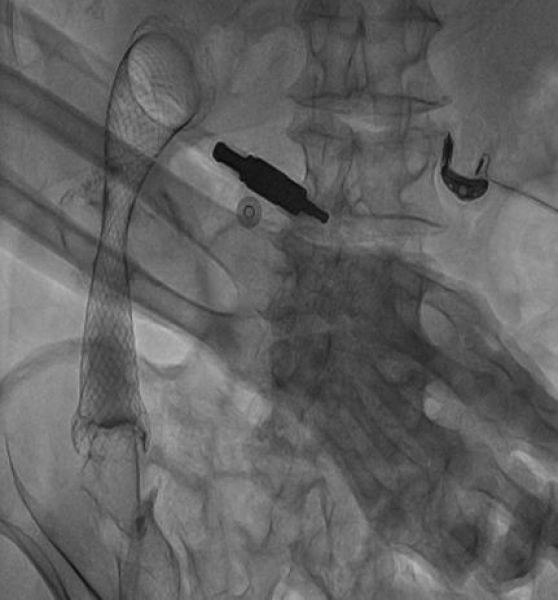

置入肠道支架

成功置入肠道支架